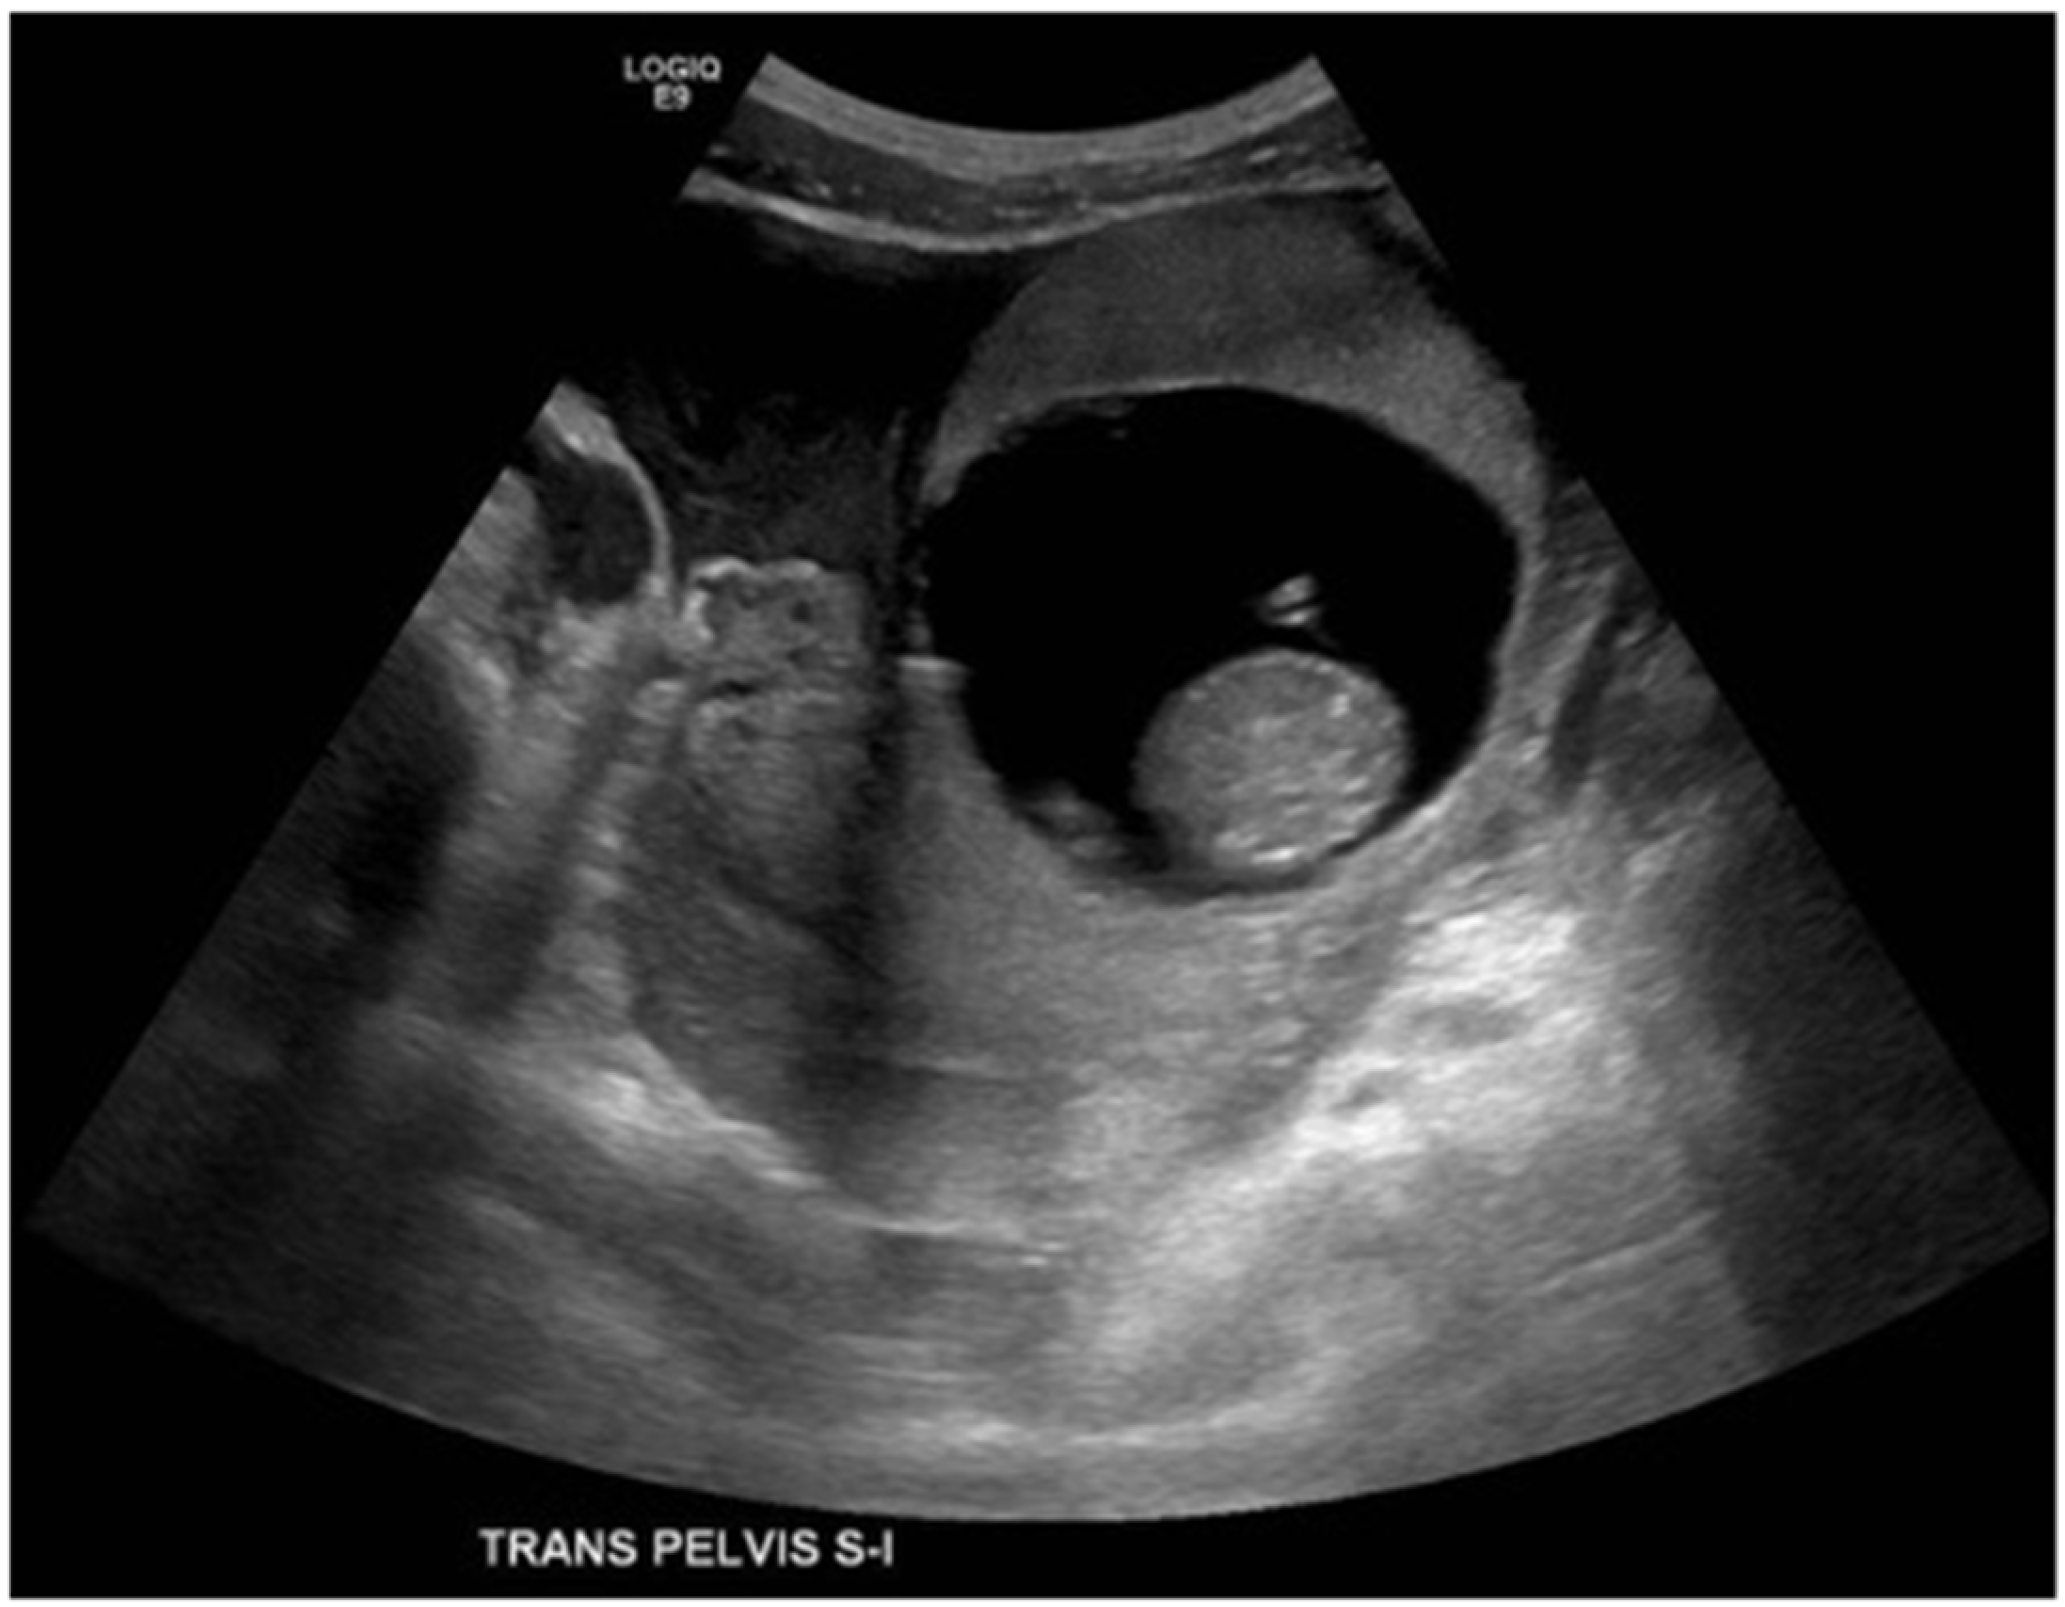

Figure 1.

A 33-year-old female presented with diffuse abdominal pain. Transverse ultrasound of the pelvis through the level of the uterus demonstrating gestational sac outside of the uterus and free pelvic fluid. Estimated live extrauterine gestational age of 13 weeks 6 days +/− 1 week 2 days. It is unclear whether the ectopic pregnancy is located within the left fallopian tube or involves the left ovary.